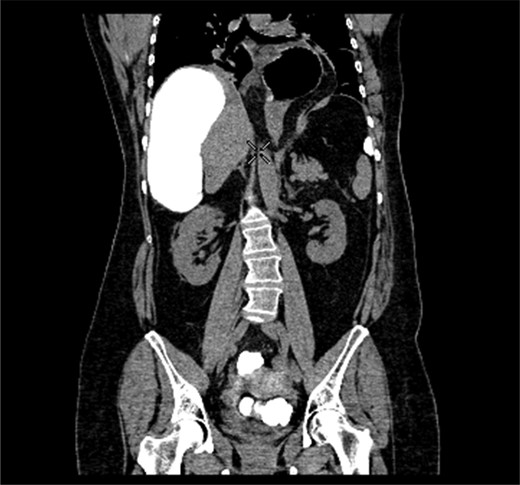

A 58-year-old female with a past medical history of a large intrathoracic hiatus hernia presented to her general practitioner and was subsequently referred to our surgical department with symptoms of sudden onset severe epigastric pain associated with vomiting and abdominal distension. Her abdomen was generally tender, maximally in the epigastric region, although she was not peritonitic. The admission erect chest radiograph showed a large hiatus hernia and an elevated right hemidiaphragm with a large loop of distended bowel (Fig. 1). Subsequent computed tomography (CT) scan demonstrated an almost completely intrathoracic stomach with a degree of volvulus, and the liver medially displaced by a loop of large bowel felt to be caecum (Fig. 2). Since the patient remained otherwise well, bidirectional endoscopy was performed, and given that a volvulus point could not be identified and the ileocaecal junction was not identified, contrast studies were requested (Figs 3–5) which demonstrated an incomplete obstruction caused by a volved caecum rotated anteriorly and cephalad.

CT coronal section demonstrating caecum medially displacing the liver and causing an upward pressure on the right hemidiaphragm.

Coronal section of contrast-enhanced CT demonstrating contrast filling upwardly displaced caecum.

Radiological imaging is useful in diagnosing caecal volvulus. Rosenblat et al. [8] found that CT findings of whirl, ileocaecal twist, transition points, X marks the spot and split wall have high specificity for caecal volvulus. Additionally, they found that the absence of distal colonic decompression made the diagnosis of caecal volvulus unlikely. Diagnostic confusion may exist between sigmoid and caecal volvulus; however, the location of the mesenteric twist (CT whirl sign) is highly accurate in distinguishing the two [9]. This whirl sign, as first published by Fisher [10], describes ‘swirling strands of soft tissue attenuation within a background of fat attenuation and gives the appearance of a hurricane on a map’. Barium enema has been historically used to confirm the presence of a volvulus, assess the distal colon and may also have a therapeutic effect [3].